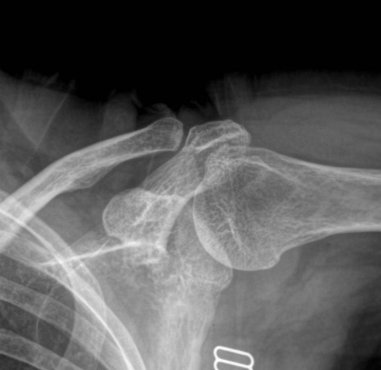

¹æ»ç¼± °Ë»ç : ¾î±ú ÀÜ¸é »çÁø¿¡¼ ´ë°áÀýÀÇ ¹Ì¼¼ÇÑ °ñ±Ø°ú °æÈµÈ ¼Ò°ßÀ» º¸ÀÌ°í °ßºÀ ÇÏ´ÜÀÇ °æÈ ¼Ò°ß ¹× ¿À±¸µ¹±â °ßºÀÀÎ´ë ºÎÂøºÎ °ñ±ØÀ» º¸¿© ¸¸¼ºÀûÀÎ Ãæµ¹ÀÌ ÃßÁ¤µÊ. ¿ÜÀü½Ã Àü¸é »çÁø¿¡¼ ´ë°áÀýÀÌ °ßºÀÇÏ´Ü¿¡ Á¢ÃËÇÏ´Â ¸ð½ÀÀÌ °üÂûµÊ.

Ãæµ¹ÀÌ ÁøÇàµÇ¸é ´Ü¼ø¹æ»ç¼± ÃÔ¿µ¿¡¼µµ Ãæµ¹ÀÇ ÈçÀûÀ» ¹ß°ßÇÒ ¼ö ÀÖ´Ù. ´Ü¼ø¹æ»ç¼± ÃÔ¿µ¿¡¼ ´ë°áÀýÀ̳ª °ßºÀÀÇ °æÈ¼º º¯È(sclerotic change) ¶Ç´Â °ñ±Ø, ´ë°áÀûÀÇ °ñ °á¼ÕÀÌ °üÂûµÇ¸é Ãæµ¹ÀÌ ¸¸¼ºÀûÀ¸·Î ÁøÇàµÇ¾úÀ½À» ½Ã»çÇØÁØ´Ù. °ßºÀ¼â°ñ°üÀý ÇÏ´ÜÀÇ °ñ±ØÀ̳ª caudal tilt ÃØ¿µ¿¡¼ º¸ÀÌ´Â °ßºÀÀÇ °ñ±ØÀ» °üÂûÇϸé Ãæµ¹ ¹ß»ý °¡´É¼ºÀ» ÃßÁ¤ÇÒ ¼ö ÀÖ°í ¿À±¸µ¹±â°ßºÀÀÎ´ë °ßºÀ ºÎÂøºÎ¿¡¼ º¸ÀÌ´Â °ñ±ØÀº ȸÀü±Ù°³ ÆÄ¿À» °·ÂÈ÷ ½Ã»çÇÏ´Â ¼Ò°ßÀ̰í ÀÌ·± °æ¿ì ´ë°³ º¸Á¸Àû Ä¡·á¿¡ ¾çÈ£ÇÑ È£ÀüÀ» º¸ÀÌÁö ¾Ê´Â´Ù. ÀüÈĹæ»çÁø¿¡¼ critical shoulder angleÀ» °üÂûÇÑ´À ½À°üµµ ¸Å¿ì À¯¿ëÇÏ´Ù(»çÁø 4).